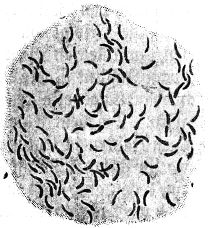

Abb. 2

Abb. 2.

Ausstrichpräparat von menschlichem Zahnschleim, gefärbt, etwa 1000fach vergrößert. Mannigfaltige Bakterien in buntem Gemisch.